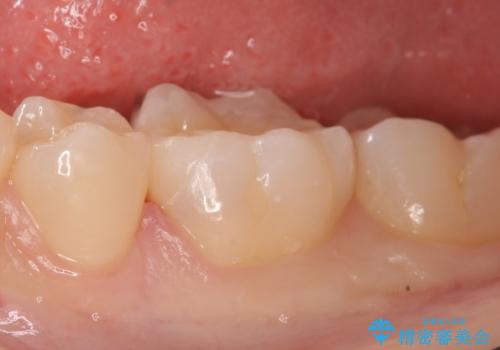

古い樹脂と虫歯を除去後、セラミックインレーによる修復を行いました。

当院のセラミックインレーはemaxという強度と審美性に優れた材料を使用しています。

またプレス方式でインレーを製作しているため、削り出しで製作するCADCAMより優れた適合性も持ち合わせており、虫歯が再発しにくい修復物です。